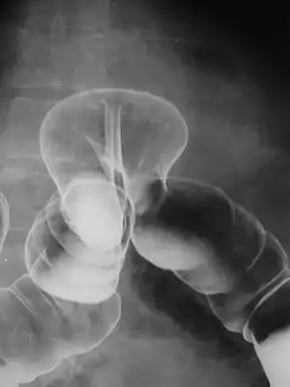

![]() Radiograph of a barium enema displaying a colonic herniation. | |

A lower gastrointestinal series is a medical procedure used to examine and diagnose problems with the human colon of the large intestine. Radiographs (X-ray pictures) are taken while barium sulfate, a radiocontrast agent, fills the colon via an enema through the rectum.